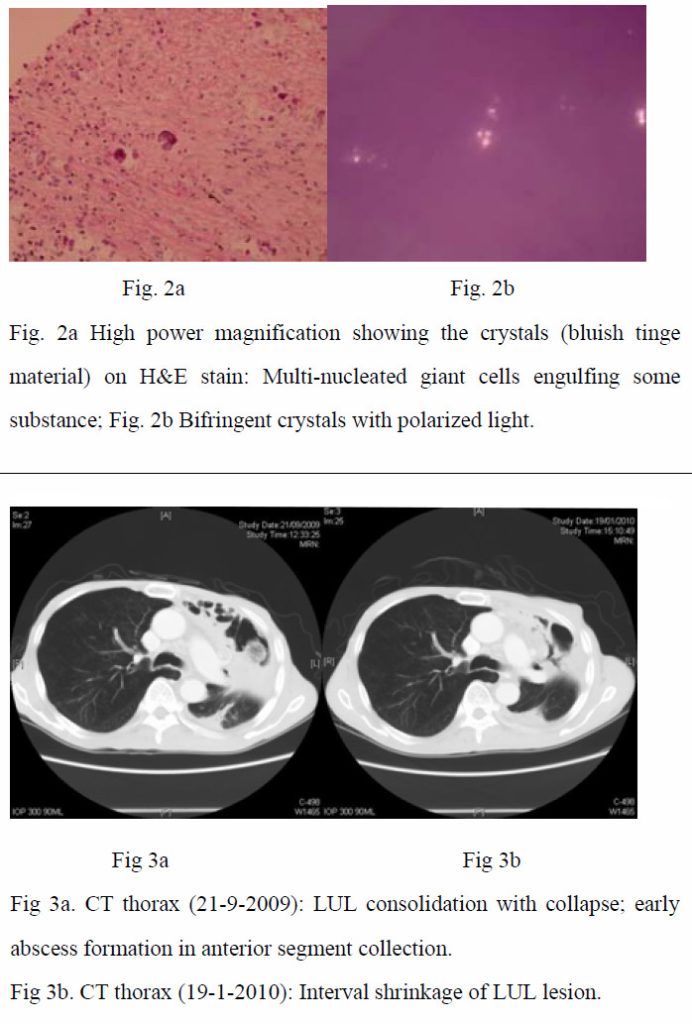

As the condition did not improve and pulmonary tuberculosis was a differential diagnosis with the CXR appearance, empirical anti-tuberculous treatment was started (isoniazid, rifampicin, ethambutol, pyrazinamide) on 4th September 2009. CT-guided biopsy of the lung lesion was subsequently performed. While culture of the biopsy was negative, histology report revealed inflammation, fibrosis, and foreign body giant cell reaction against crystal–like foreign body, nature of which was unknown. It was negative for malignancy and fungal stains (PAS/PASD and Grocott). X-ray microanalysis and the appearance of the crystals under electron microscopy were suggestive of presence of calcium oxalate crystals. (Fig. 2a and 2b) More in-depth history was elicited. Although the patient was a tour guide before the admission, he had worked in a construction site with respirator on for 10 days 8 years ago. He denied history of intravenous drug addiction or inhalational drug abuse. There was no choking on eating. Ophthalmologist was consulted to look for any crystallinopathy or embolism in the fundi, which were absent. Oxalate level in 24-hour urine was 0.32 mmol/day (normal range 0.08-0.49 mmol/day), making possibility of hyperoxaluria less likely.

In the presence of inflammatory reactions against calcium oxalate crystals on lung biopsy and the settings of unresolved pneumonia despite multiple antibiotics, the clinical diagnosis of chronic necrotizing pulmonary aspergillosis with pulmonary oxalosis was reached. Voriconazole was started on 1st October 2009. Low grade fever persisted during the first 10 days of treatment. Voriconazole was then replaced by amphotericin B, when the fever eventually subsided. C-reactive protein checked on the ninth day of voriconazole treatment later revealed marked reduction from 146.0 mg/L on 30th September 2009 to 67.7 mg/L on 9th October 2009, which was suggestive of an improvement. Voriconazole was thus resumed. The patient remained afebrile and C-reactive protein went on a downward trend. The patient was subsequently discharged with oral voriconazole. Aspergillus antibody was rechecked, which was positive after discharge. During subsequent outpatient visits, the patient remained afebrile, with improved exercise tolerance and decreased respiratory symptoms. Voriconazole was then changed to itraconazole on 1st February 2010 after cost-effectiveness evaluations. Improvement was continually noted in CRP trend, on CXRs and CT thorax with time (Fig 1, Fig 3a and 3b).

In our case, we were given the clue of having crystals in the lungs. According to literature, there are only a few types of crystals in lungs. Charcot-Leyden crystals are eosinophilic structures typically rhomboidal or needle-shaped crystalline by-products of eosinophil granules1 and can be found in hyper-eosinophilia states like asthma and fungal infections.1 Calcium salts like calcium oxalate can be found in fungal infections such as aspergillosis and zygomycosis.5,6,7 Intravascular crystal-like embolus is the third type of crystals present in lungs.3 These can arise from vascular manipulations like vascular surgery.3 In patients with crystal-storing histiocytoma, paraprotein accumulation within the cells accounts for the presence of crystals 4

Calcium salts have been found in fungal infections. While they are usually found in aspergillosis, they have also been mentioned in some case reports of zygomycosis.5,6,7 Amongst the calcium salts, calcium oxalate has been the most commonly identified component.5,6,7 In humans, a direct association has been found between oxalate crystal production and Aspergillus niger or less often Aspergillus fumigatus infection.11 It has been reported that calcium oxalate is a fermentation product of Aspergillus species via the tricarboxylic acid cycle.2,11 Such crystals, as suggested by Yoshihisa et. al., could cause damage to the lung tissue.2 Such damage may lead to fatal pulmonary haemorrhage.11 In addition to the lung tissue, it has been reported that calcium oxalate is also present in sputum. Together with serological assays, this might give the hint for early diagnosis of aspergillus pneumonia. 2